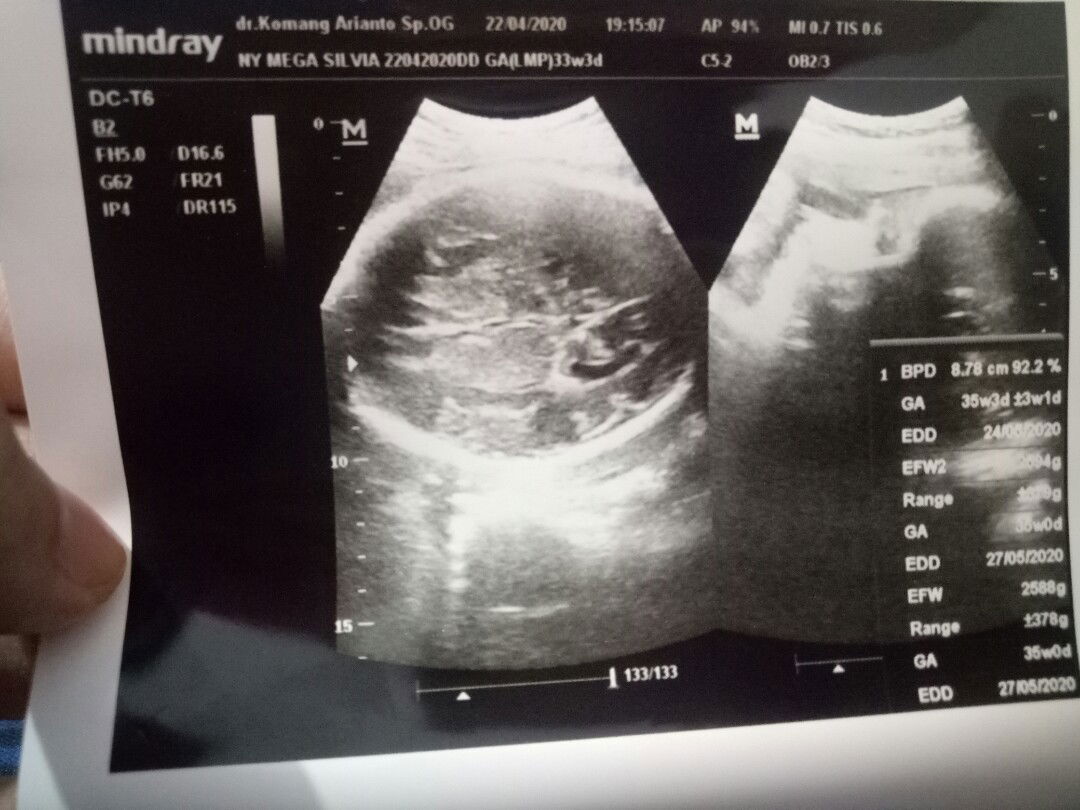

usia dan bb janin

Mau tanya bun, Ada yg bisa baca hasil usg nya gak? Soalnya tadi dokternya buru buru karna dokternya mau ada operasi.. Jadi tadi hanya tanya point2 penting saja.. Di hasil usg bagian atas kan usia janin 33minggu 3hari tapi dibagian kanan usia janin 35minggu 3hari yg benar yg mana ya ? Dan 31w1d maksudnya apa ya bun? Dan Bb janin 2594 gram normal atau kegedean untuk usia kehamilan 33 minggu? Mohon bantu dijawab ya bun Terima kasih